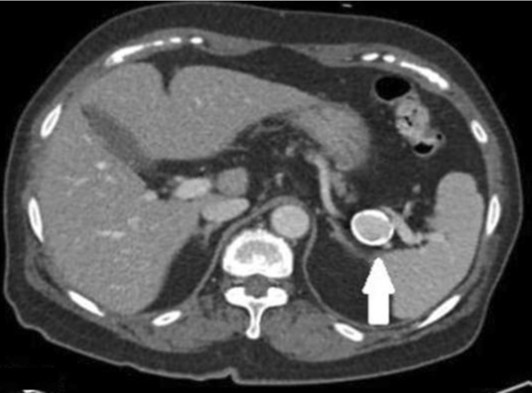

Fig. 1.

The axial CT image shows 2.5cm sized aneurysm (white arrow) with calcification in the splenic artery at the hilum of spleen.

CT상 비장의 hilum의 위치에 2.5 x 2 cm 크기의 타원형의 mass like lesion이 관찰되었고 splenic artery와 연결되고 splenic artery와 동일한 조영증강을 보여 동맥류로 추정되었으며 rim calcification이 동반되어 있었음 (Fig.1). 정확한 해부 구조를 보기 위해 시행한 CT angiography에서 비장의 hilum의 근처 splenic artery 원위부에 동맥류가 관찰되었고 동맥류로부터 두 개의 큰 branching vessels이 기시하고 있었다 (Fig.2).